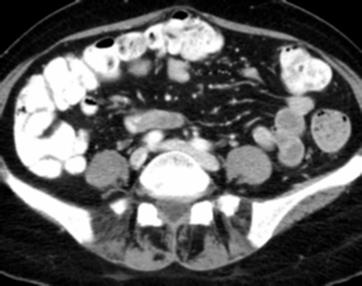

Due to the constraints of the imaging device and high cost in operation time, computer tomography (CT) scans are usually acquired with low intra-slice resolution. Improving the intra-slice resolution is beneficial to the disease diagnosis for both human experts and computer-aided systems. To this end, this paper builds a novel medical slice synthesis to increase the between-slice resolution. Considering that the ground-truth intermediate medical slices are always absent in clinical practice, we introduce the incremental cross-view mutual distillation strategy to accomplish this task in the self-supervised learning manner. Specifically, we model this problem from three different views: slice-wise interpolation from axial view and pixel-wise interpolation from coronal and sagittal views. Under this circumstance, the models learned from different views can distill valuable knowledge to guide the learning processes of each other. We can repeat this process to make the models synthesize intermediate slice data with increasing inter-slice resolution. To demonstrate the effectiveness of the proposed approach, we conduct comprehensive experiments on a large-scale CT dataset. Quantitative and qualitative comparison results show that our method outperforms state-of-the-art algorithms by clear margins.